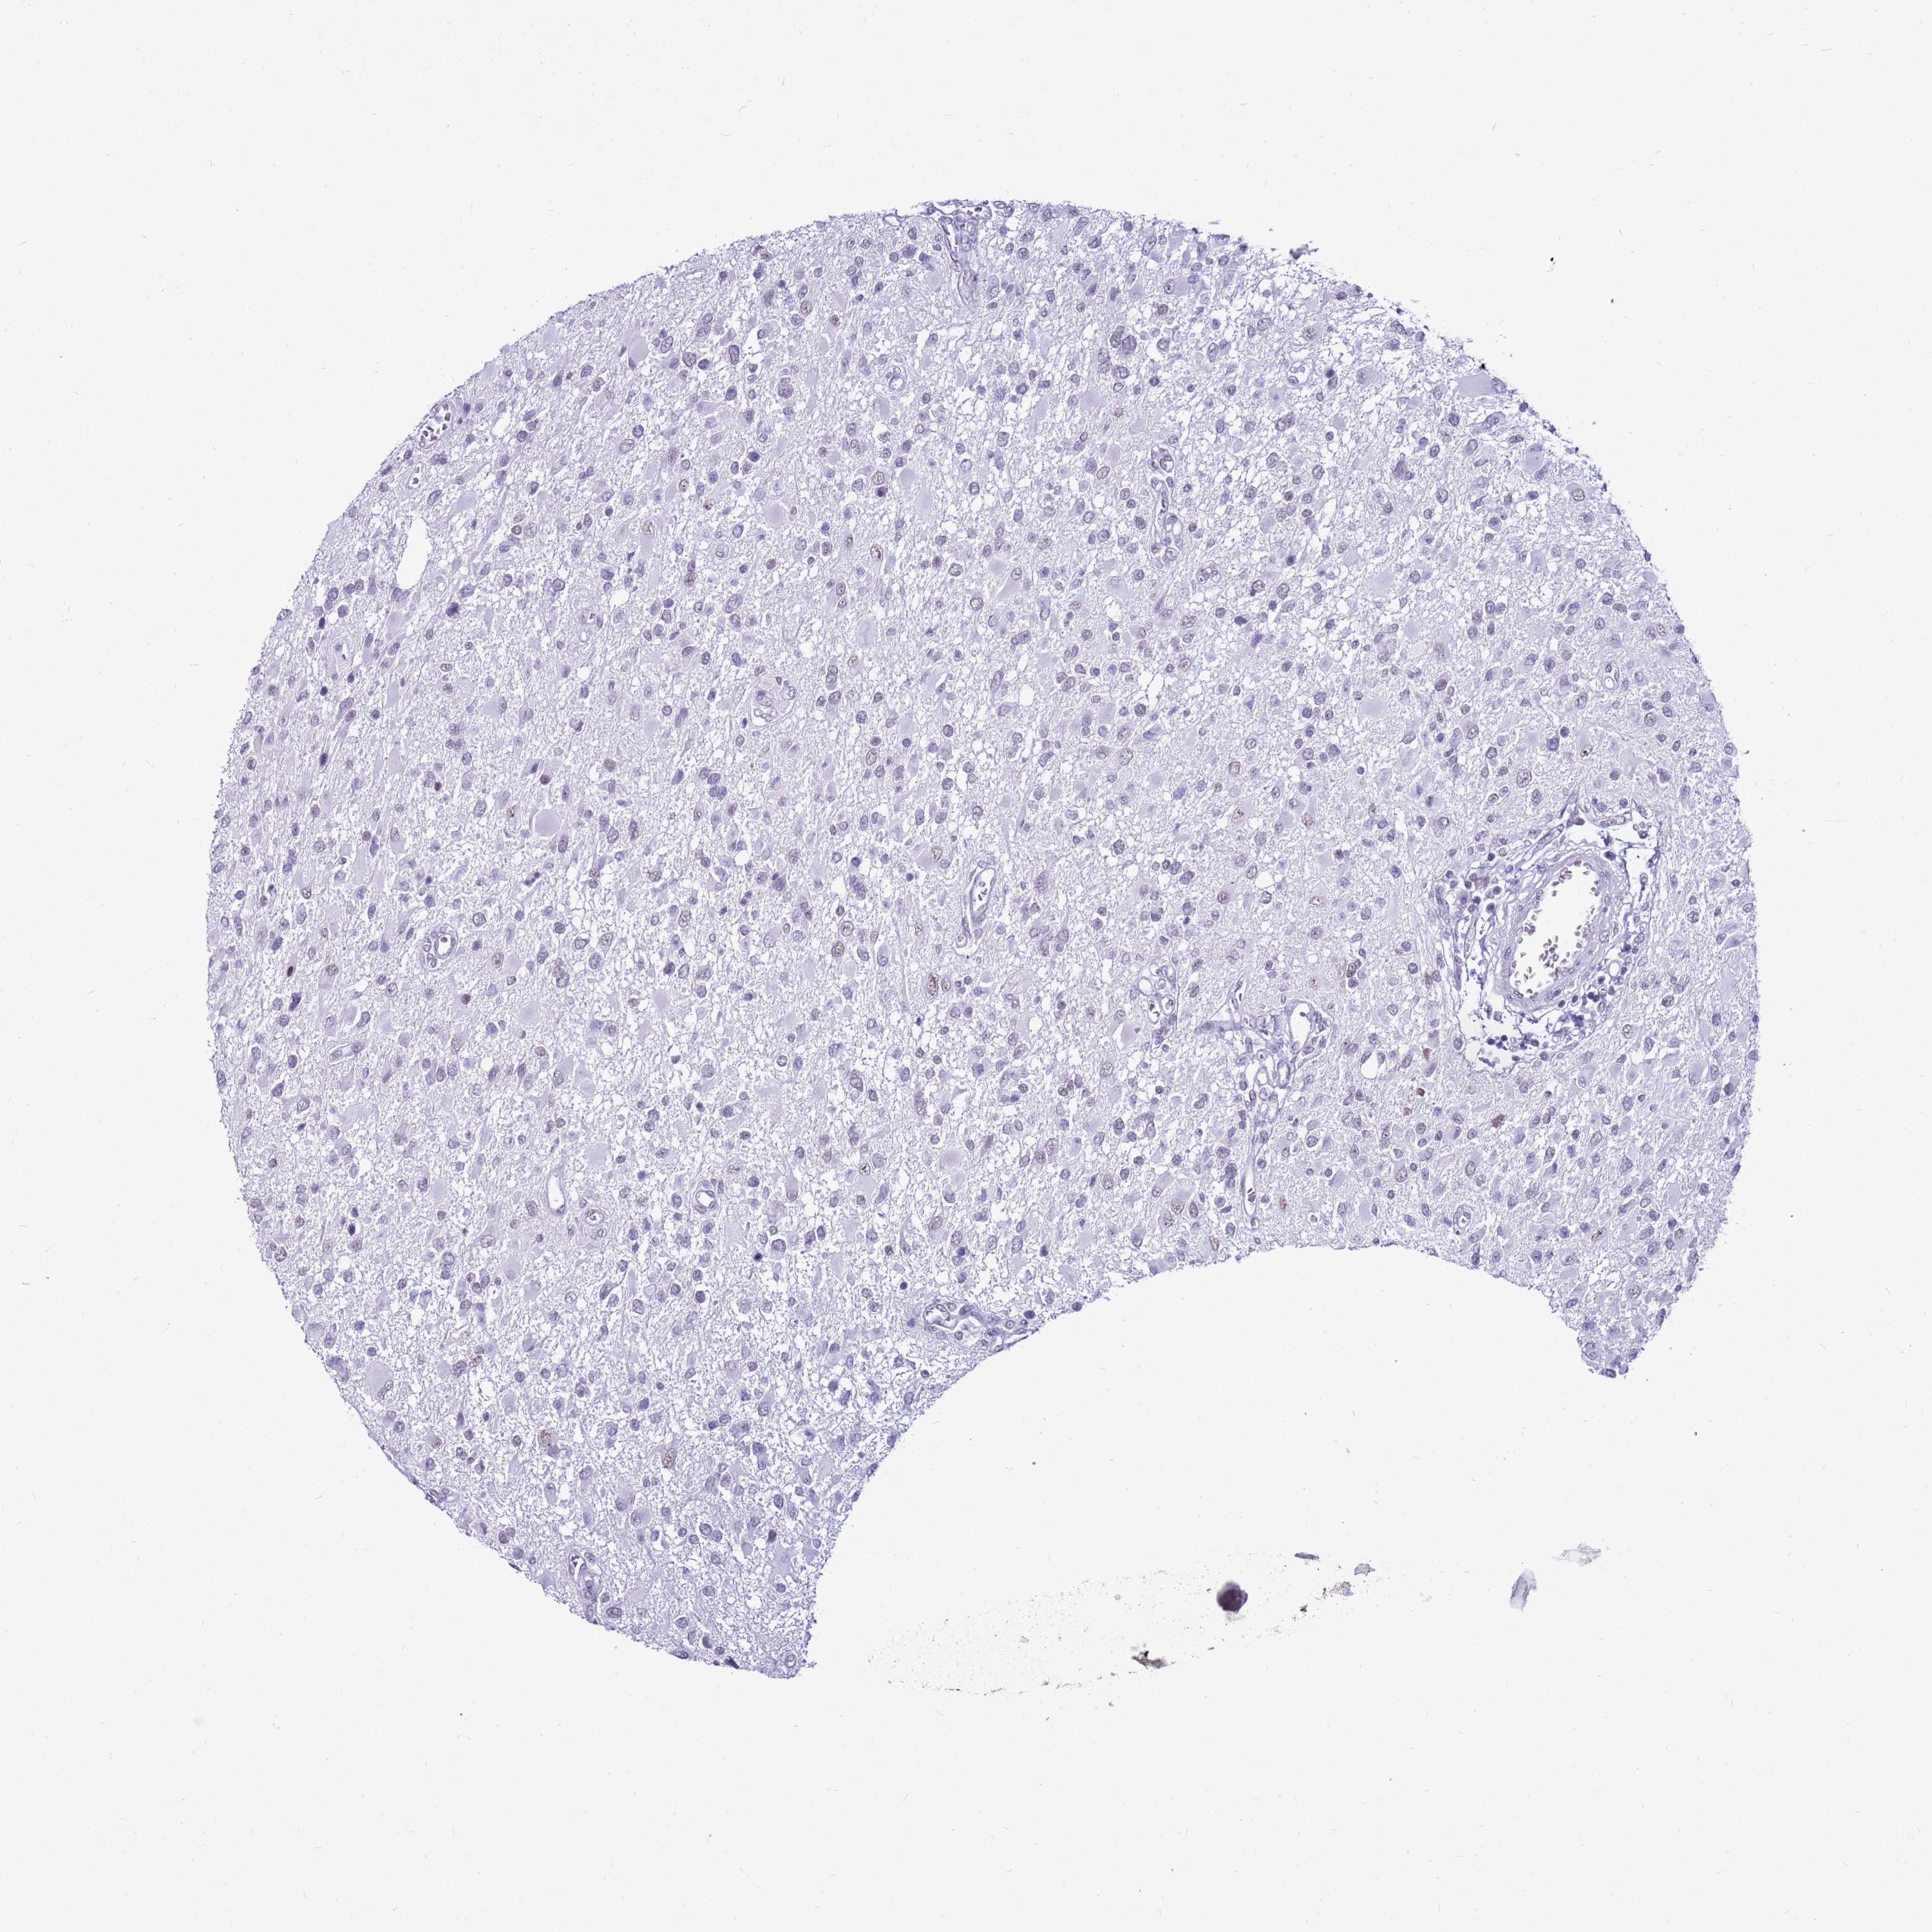

GLIOMA - Protein expressioni

A mouse-over function shows sample information and annotation data. Click on an image to view it in a full screen mode. Samples can be filtered based on level of antibody staining by selecting one or several of the following categories: high, medium, low and not detected. The assay and annotation is described here.

Note that samples used for immunohistochemistry by the Human Protein Atlas do not correspond to samples in the TCGA dataset.

Antibody stainingi

Antibody staining in the annotated cell types in the current human tissue is reported as not detected, low, medium, or high, based on conventional immunohistochemistry profiling in selected tissues. This score is based on the combination of the staining intensity and fraction of stained cells.

Each image is clickable and will lead to virtual microscopy that enables deeper exploration of all samples and also displays staining intensity scores, fraction scores and subcellular localization as well as patient and tissue information for each sample.

Antibody HPA047047

Staining

High

Medium

Low

Not detected

Intensity

Strong

Moderate

Weak

Negative

Quantity

>75%

75%-25%

<25%

None

Location

Nuclear

Cytoplasmic/membranous

Cytoplasmic/membranous,nuclear

Glioma, malignant, High grade

Glioma, malignant, Low grade